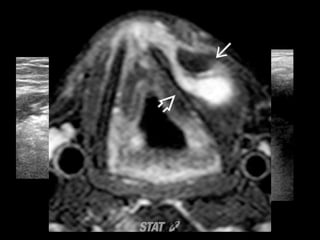

LARINGOCELE

LARINGOCELE • Evaginación dela mucosa normal laringea que se proyecta superiormente desde ventrículo laríngeo. • Contiene numerosas glándulas mucosas • laringocele interno: – Aire dilatada o laríngea sáculo lleno de líquido – Situado en el espacio paraglótico de supraglotis